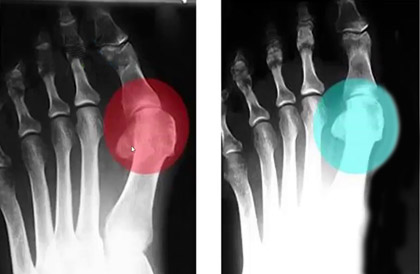

До использования

После 1,5 месяца использования шины RelaxFoot

С целью устранения Hallus valgus (бурсита) и негативных симптомов, сопровождающих деформацию ступней, успешно применяется магнитотерапия. Магнитотерапия – уникальный метод физиотерапевтического лечения с помощью воздействия на организм постоянным, переменным или бегущим магнитным полем. Процедура является безопасной и не вызывает болезненных ощущений.

Чтобы купировать воспалительный процесс, достаточно использовать магнитную шину RelaxFoot ежедневно в течение 3-5 часов. Это способствует не только выравниванию фаланг пальцев и уменьшению деформации, но также благодаря воздействию магнитов происходит стимуляция нервных окончаний, повышается тонус тканей, улучшается кровообращение. RelaxFoot фиксирует большой палец в нужном положении, снижает нагрузку на ступни, купирует боль, облегчает ходьбу и возвращает здоровья ступням.